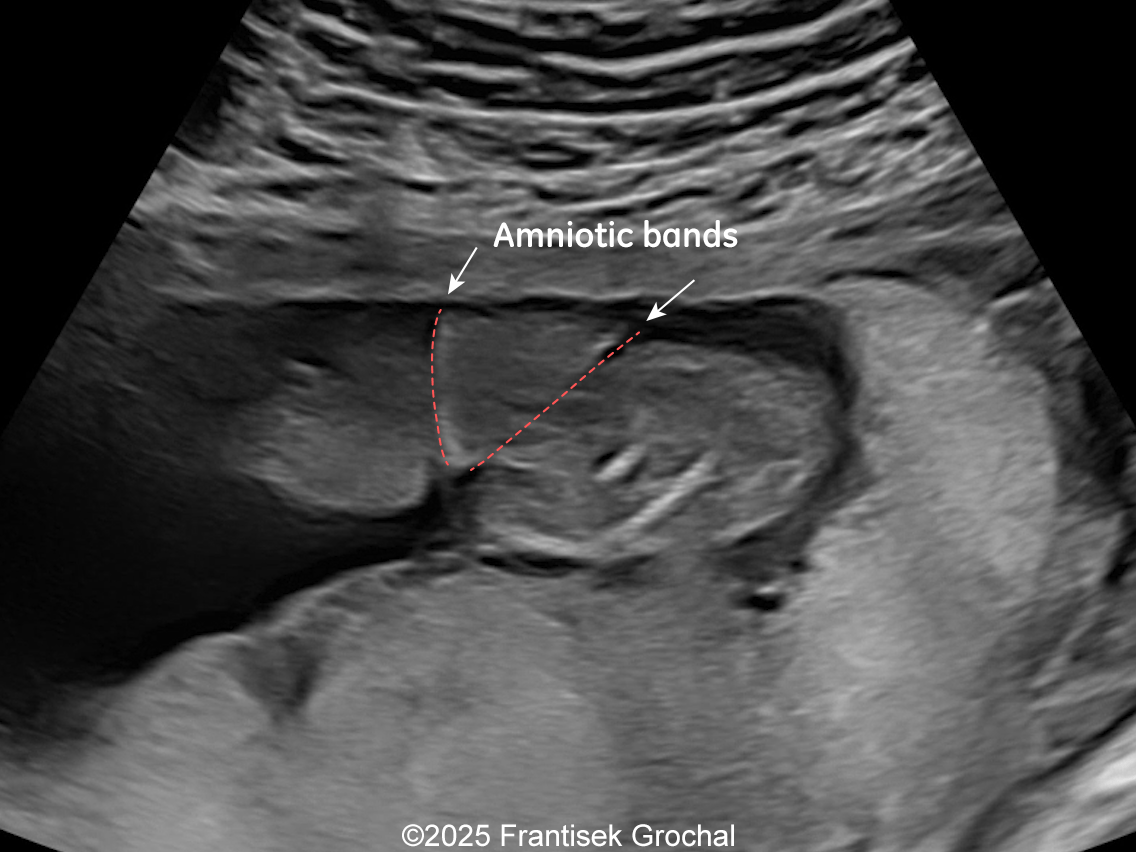

We present a case of Amniotic Band Sequence seen in 21st week of pregnancy. The fetus showed the following findings:

- Constriction of the right thigh by the amniotic band

- Constriction of fetal torso by two strips of amniotic band

Prenatal ultrasound imaging shows thin echogenic bands attaching to both the uterine wall and associated fetal structures. The bands themselves can be difficult to detect, hence the visualization of bands is not required to suggest the diagnosis. Random anomalies that do not follow a pattern should lead the clinician to suspect amniotic band sequence and prompt close evaluation for a causative band [5, 6]. The defects resulting from the bands are categorized into various categories: neural tube-like defects, craniofacial anomalies, limb anomalies, abdominal and thoracic wall defects, and visceral anomalies [7, 8]. The most common findings are those caused by constriction rings in the limbs, which are present in at least 80% of cases. They may vary in depth, involving only the skin, to involving bone and causing edema of the distal limb, extremity asymmetry, pseudosyndactyly, or amputation of limbs or digits [8]. Histologically, constriction bands are composed of fibrous tissue containing fibroblasts covered by squamous cells, which may make them inelastic and produce a ligature effect [9]. Clubfoot deformity of the lower extremity is found in up to one third of cases, probably secondary to the presence of oligohydramnios if there is loss of amniotic fluid [6].

Differential diagnosis includes other conditions that produce intrauterine linear echogenicities in the gravid uterus: uterine synechiae with amniotic sheets, uterine duplication anomalies, chorioamniotic nonfusion or separation, and circumvallate placenta [17]. Unlike amniotic bands, synechiae may have blood flow detected with Doppler, do not restrict fetal movements and are not associated with fetal abnormalities.